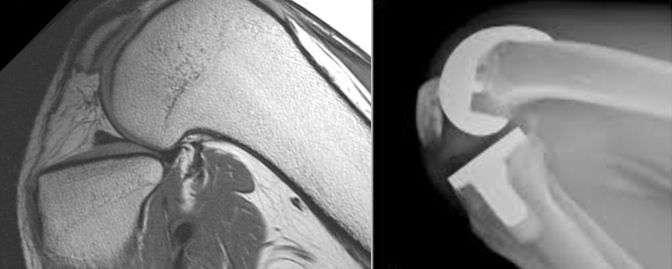

Interestingly the angle between the posterior condylar line (PCL) and the Anterior Trochlea Line (ATL) differ only little (2° +- 3° IR ) [44]. This shows that the posterior axial deformity (PCL) and the anterior axial deformity (ATL) are linked and this might compensate for patella tracking in knees with posterior knee axial deformity [45]. On the other hand, there is a wide variation of the posterior condylar axis to the TEA [2,6,7,27,29,31,32,46] showing that any posterior axial deformity of the femur cannot be compensated for the tibiofemoral joint and ends up with valgus malalignment under loading and lateral flexion gap opening under unloaded conditions. For these cases with distal femur torsional deformities, it needs to find a compromise to correct the axial plane by performing proper rotational bony correction cuts. The key point to prevent rotational malignment of the femur component is to identify axial plane deformities of the distal femur before and correct them during TKA surgery. On standardized AP and lateral radiographs these axial plane deformities cannot be identified. With special axial kneeling views, they might be identified, but are very depended on the right technique used [47]. The golden standard for the identification of femur axial plane deformities is still CT or MRI imaging (Fig 1) [2].

Some surgeons recommend to routinely perform 3-D analysis before surgery, and this is mandatory for surgeons using patient specific cutting blocks and robotic surgery. This 3-D planning allows not only to identify any axial plane deformity of the femur and tibia before surgery but also makes proper correction during surgery easier and more reproducible. We do not routinely plan the axial plane with CT or MR imaging. History, clinical examination and axial weight bearing patella views are routinely used to identify any patella maltracking or asymmetric flexion gap. Only in cases with complex patella dislocations, we perform a rotational profile with MR imaging, to identify where the axial plane deformity is located (femur, tibia or both) (Fig 14).

On standardized AP and lateral radiographs these axial plane deformities cannot be identified. The golden standard for the identification of proximal tibia axial plane deformities is still CT or MRI imaging (Fig 23 A and B) [5,30].

Some surgeons recommend to routinely perform 3-D analysis before surgery, which allows not only to identify any axial plane deformity of the femur and tibia before surgery but also makes proper correction during surgery easier and more reproducible [7]. We do not routinely plan the axial plane with CT or MR imaging. Only in cases with complex patella dislocations, we perform a rotational profile of the knee with MR imaging, to identify where the axial plane deformity is located (distal femur, proximal tibia or both) (Fig 14).